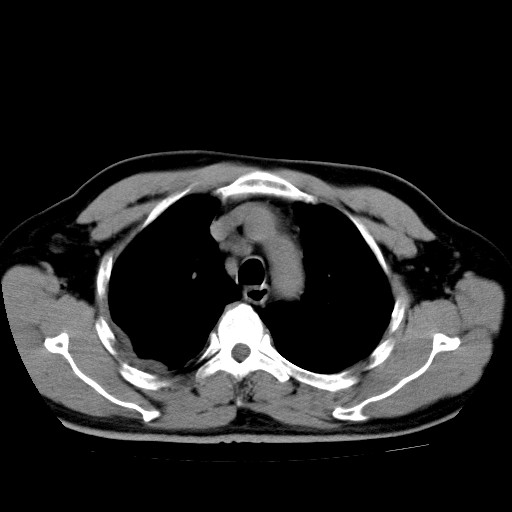

男,54岁,咳嗽,右侧胸痛10天。肺窗>150k,传不了

右肺中心型肺癌并右下肺不张,右侧胸膜纵隔转移。

右中央型肺癌并右肺下叶不张,纵隔内及右胸膜转移,右胸腔积液

考虑   右肺癌伴右下肺部分不张,阻塞性肺炎,纵隔淋巴结增大,右侧胸腔积液其他待排

考虑右肺下叶中央型肺癌并右肺下叶不张,纵隔淋巴结内及右胸膜转移。建议增强。

右下叶大片实变,肺门未见明显肿块影。有胸腔积液和纵隔内肿大淋巴结影。没有增强和肺窗,不好定。

考虑:1、右下叶周围型肺癌伴胸膜、纵隔淋巴转移?

右下叶大片性阻塞性肺炎,肺门未见明显肿块影,纵隔内可见肿大淋巴结影,右见右侧胸腔积液及右侧胸膜增厚。

考虑:右侧中心性肺癌?伴纵隔淋巴结转移。建议上传肺窗。